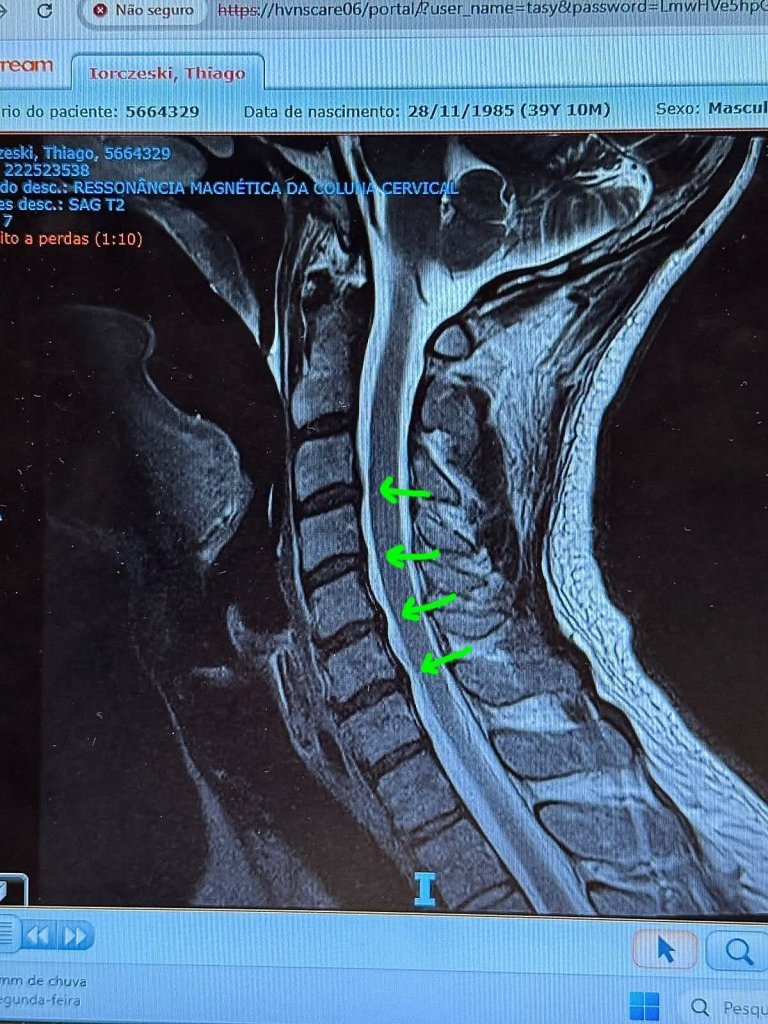

Tiago Iorc foi internado às pressas neste final de semana após sentir fortes dores na região cervical. Neste domingo, 12, ele contou que realizará um procedimento médico com injeções contra a dor após ser diagnosticado com uma crise de hérnia de disco na cervical. O cantor descreveu que o problema de hérnia de disco aconteceu por causa de sua má postura ao longo da vida, o que levou ao problema na estrutura de amortecimento das vértebras.